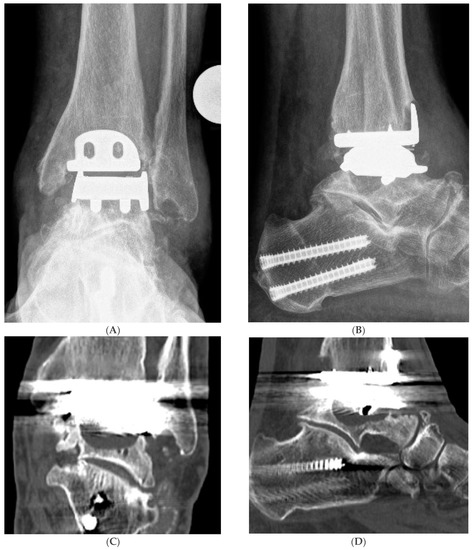

Hybrid Total Ankle Arthroplasty (H-TAA). This figure represents Case Nr. 7 of the cohort (see Table 1, Table 2 and Table 3). (A–D): Preoperative X-rays and CT-scans depicting the cyst under the talar component of the Hintegra TAA. (E,F): Intraoperative pictures showing the inlay breakage with poor bone osteointegration in the backside of the talar component of the Hintegra TAA. (G): Talar cyst with stable tibial Hintegra component. (H): Performance of a flatcut of the talus and bone grafting of the talar cyst with iliac crest autologous spongiosa. (I): Flatcut Talar Component of the VANTAGE TAA, which is implanted on the reconstructed talus. (J): H-TAA: Tibial component Hintegra TAA with new Flatcut Talus and Inlay of VANTAGE TAA. (K,L): Postoperative X-rays with H-TAA, good talar bone reconstruction, and good integration of the Flatcut Talus of VANTAGE TAA.

All the patients were scored clinically and radiologically before the revision H-TAA surgery. Clinically, pain (VAS Pain Score 0–10), Dorsiflexion/Plantarflexion (DF/PF) Range of Motion (ROM; degrees), the American Orthopaedic Foot and Ankle Society (AOFAS) Ankle/Hindfoot Score (0–100 points), and Sports Frequency Score [9] (level 0–4: level 0: No sports activity; level 1: Moderate level of sports activity in leisure time, <1 h/week; level 2: Normal level of sports activity in leisure time, 1–5 h/week; level 3: High level of sports activity in leisure time, >5 h/week; level 4: Professional level of sports activity, elite athlete) were documented. There were no preoperative signs of infection in all the cases: redness, pus, or sinus. Dorsoplantar, latero–lateral and Saltzman view X-rays were performed to study grossly the TAA, detect possible cystic formations, foot and ankle associated deformities, and the overall ankle alignment (Figure 1). A Computer Tomography CT or SPECT-CT analysis was required to assess the amount of bone loss and to rule out any tibial component loosening.

The postoperative H-TAA X-rays at follow-up showed a good talar bone reconstruction and good osteointegration of the new VANTAGE talar component in all cases (no radiolucency, no loosening). The existing tibial components were unchanged and showed no loosening. No complications or reoperations for any of the included patients were noticed.